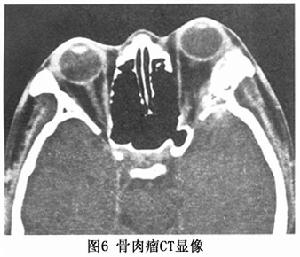

病程發展快提示眼眶惡性病變X線平片顯示明顯的骨破壞或骨化斑,輪廓不清。CT掃描對眼眶骨肉瘤的診斷價值較大,既可以顯示骨改變,又可顯示病變侵犯範圍及軟組織繼發改變。CT多具備溶骨性改變和腫塊共同存在的特徵。B型超聲檢查內回聲不均勻,形狀不規則,可伴有聲影。CDI顯示病變內有彩色血流。

2.CT掃描 長骨肉瘤一般X線片即可明確診斷,而眶骨骨肉瘤缺少特徵性典型的瘤骨及骨膜反應很少出現,與眶骨的其他腫瘤難以鑑別病變早期X線可疑骨質破壞難以確定時,CT 薄層掃描可明確有無骨質破壞,明確周圍軟組織浸潤的範圍。骨肉瘤典型的表現為眶骨局部的骨質破壞,骨結構消失,其內可有片狀高密度瘤骨,軟組織腫塊顯示清楚。腫瘤可向顱內侵犯壓迫額葉腦組織向眶內生長壓迫侵犯眼球,鄰近的眼外肌受累常顯示不清;向下侵及上頜竇甚至上齒槽骨。